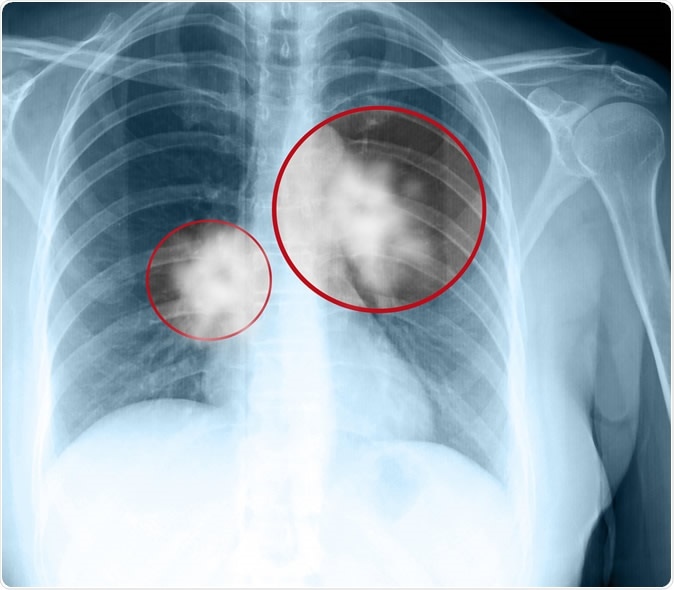

Image Credit: Muratart / Shutterstock